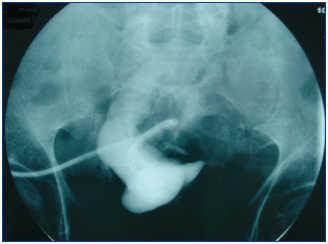

En caso de disfunción temprana del catéter peritoneal, la realización de una peritoneografía es necesaria para valorar la existencia o no de compartimentalización (figura 1).

Figura 1. Imagen de seudocavidad en la peritoneografía.